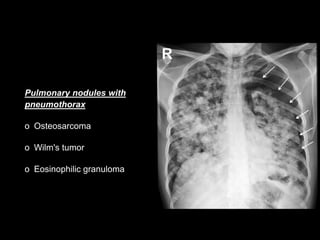

Pulmonary nodules with

pneumothorax

o Osteosarcoma

o Wilm's tumor

o Eosinophilic granuloma